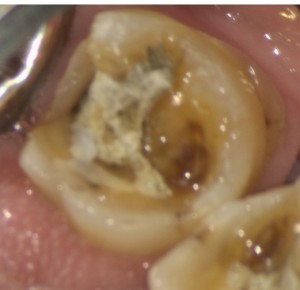

患者様は奥歯の銀歯が外れたため、白い詰め物で治したいとのことで来院されました。また、歯周病と言われたことがあり、歯ぐきの状態も含めて診てほしいとのことでした。

主訴である右下の修復治療も進めていきました。

虫歯を取り除き、プラスチックで裏層し、型取りを行います。